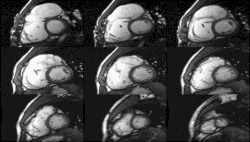

Heart function using cine imaging

Functional and structural information is acquired using bSSFP cine sequences. These are usually retrospectively-gated and have intrinsically high contrast in cardiac imaging due to the relatively high T2:T1 ratio of blood compared to myocardium. Images are typically planned sequentially to achieve the standard cardiac planes used for assessment. Turbulent flow causes dephasing and signal loss allowing valvular disease to be qualitatively appreciated. The left ventricular short axis cines are acquired from base to apex and are used for quantifying end-diastolic and end-systolic volumes, as well as myocardial mass. Tagging sequences excite a grid pattern that deforms with cardiac contraction allowing strain to be assessed.

Enlarged right ventricle with poor function in a patient with repaired tetralogy of Fallot by CMR